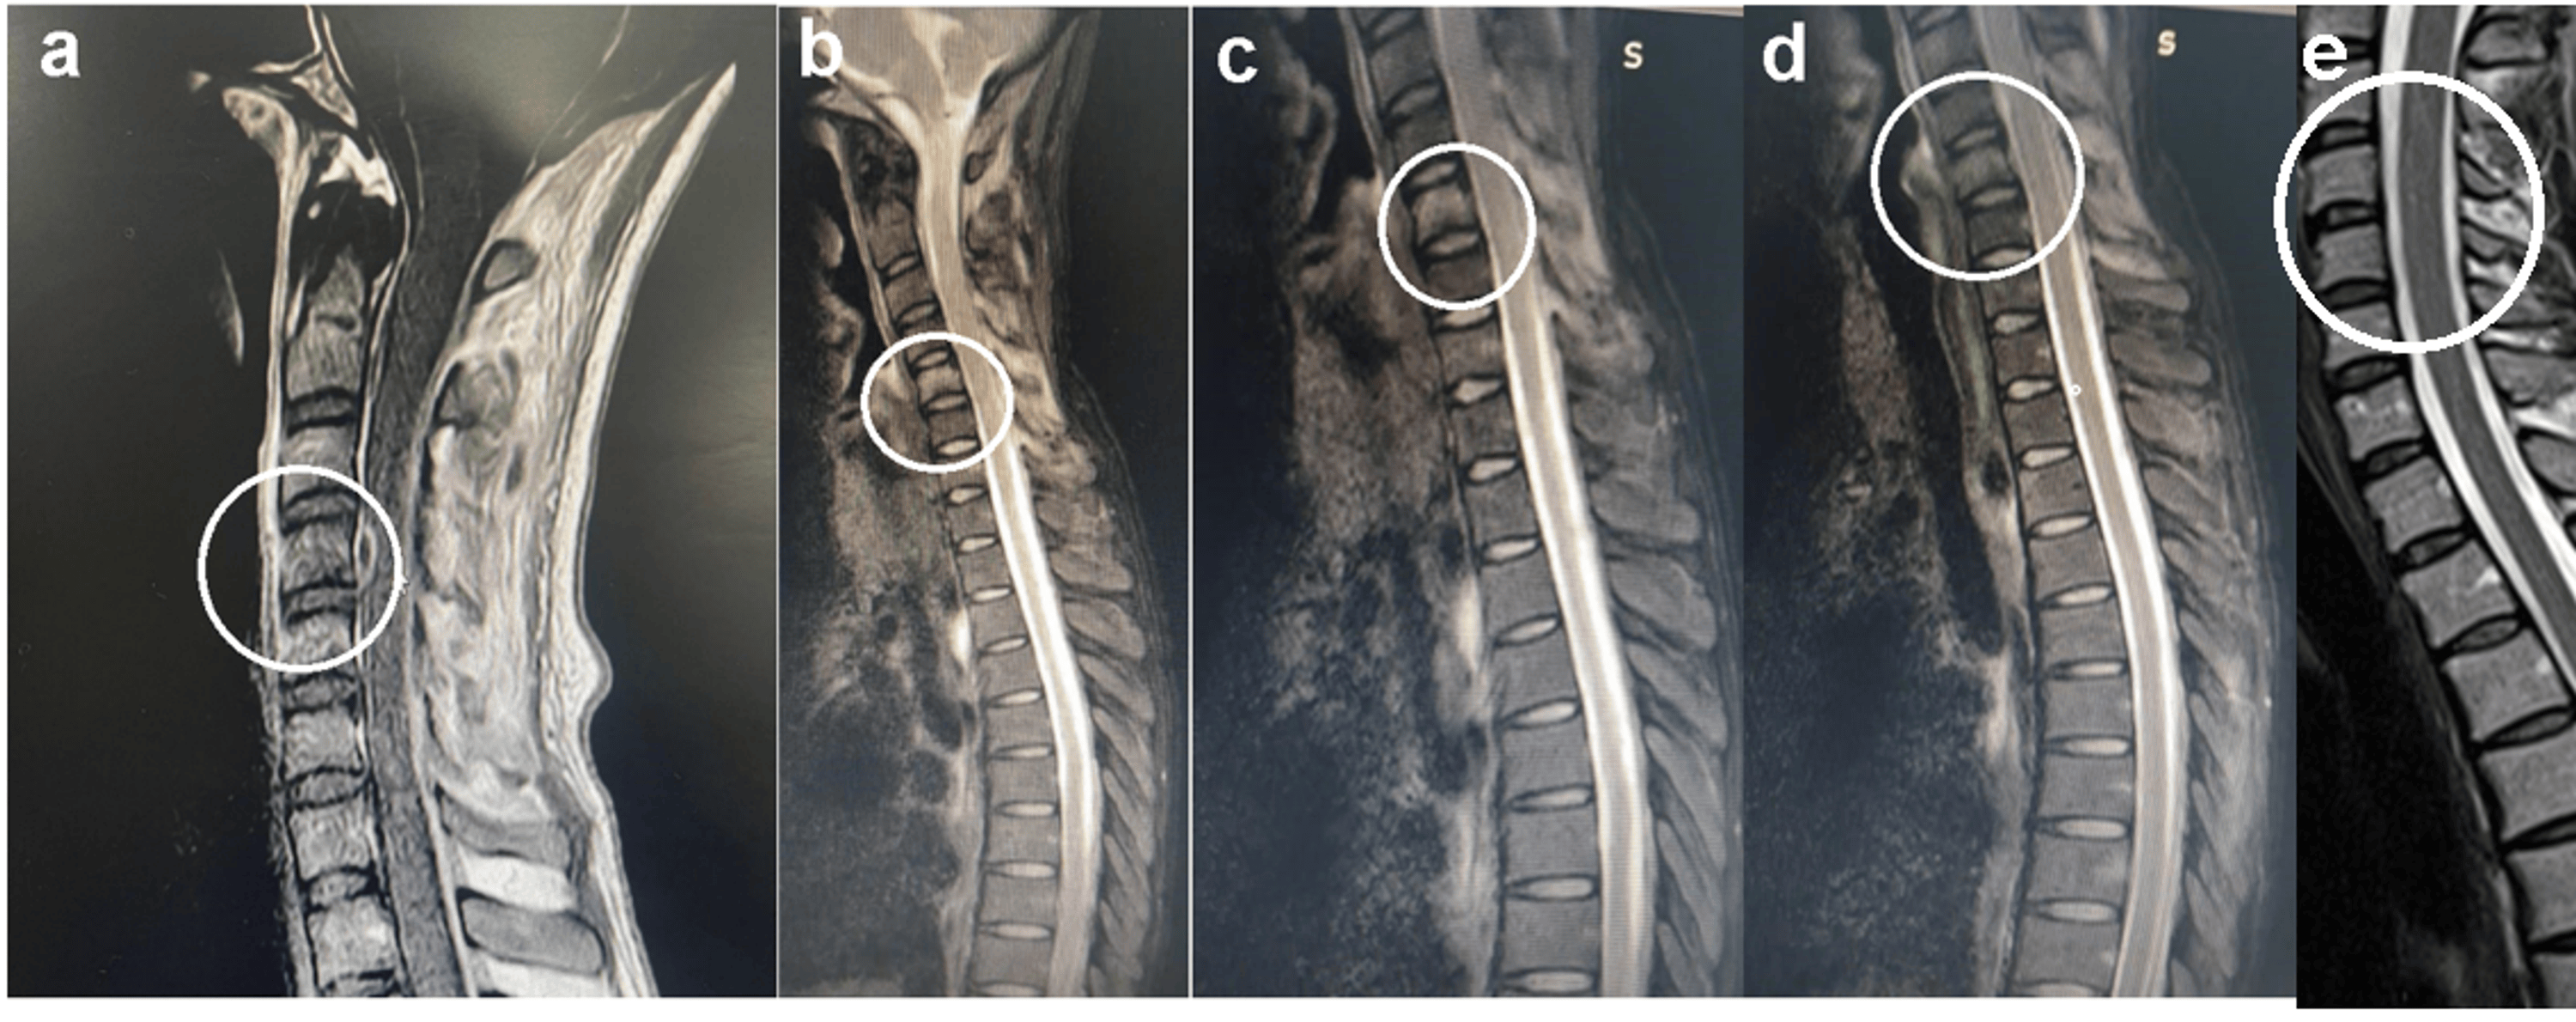

Figure 4 from A Case of Cervical Pott’s Disease Presenting as Huge Pott's Disease Cervical 5-6 Level It originates in a vertebral body and spreads to. Pott’s disease can affect any bone, or vertebra, in your spine. Tuberculous spondylitis, also known as pott disease, refers to vertebral body osteomyelitis and intervertebral discitis from tuberculosis (tb). It spreads through hematogenous route. This article discusses spinal tuberculosis—symptoms,. It usually affects more than one vertebra. Spinal tuberculosis (tb) or pott's. Pott's Disease Cervical 5-6 Level.

Figure 3 from Pott's Disease of the Cervical Spine Presenting as a Deep Pott's Disease Cervical 5-6 Level It spreads through hematogenous route. Spinal tuberculosis (tb) or pott's spine is the commonest extrapulmonary manifestation of tb. Tuberculous spondylitis, also known as pott disease, refers to vertebral body osteomyelitis and intervertebral discitis from tuberculosis (tb). This article discusses spinal tuberculosis—symptoms,. Spinal tuberculosis—also called pott's disease—is the most common type of tb affecting the bones. The spine is the most. Pott's Disease Cervical 5-6 Level.

Sagittal T2W cervical MRI showing contiguous destruction of C7 to T2 Pott's Disease Cervical 5-6 Level Tuberculous spondylitis, also known as pott disease, refers to vertebral body osteomyelitis and intervertebral discitis from tuberculosis (tb). Pott’s disease can affect any bone, or vertebra, in your spine. Spinal tuberculosis (tb) or pott's spine is the commonest extrapulmonary manifestation of tb. It originates in a vertebral body and spreads to. This article discusses spinal tuberculosis—symptoms,. It usually affects more. Pott's Disease Cervical 5-6 Level.

Figure 2 from Pott's Disease of the Cervical Spine Presenting as a Deep Pott's Disease Cervical 5-6 Level Spinal tuberculosis (tb) or pott's spine is the commonest extrapulmonary manifestation of tb. Pott disease, also know as tuberculous (tb) spondylitis, is a form of spinal infection typically caused by tuberculosis; The spine is the most frequent. This article discusses spinal tuberculosis—symptoms,. It usually affects more than one vertebra. Spinal tuberculosis—also called pott's disease—is the most common type of tb. Pott's Disease Cervical 5-6 Level.